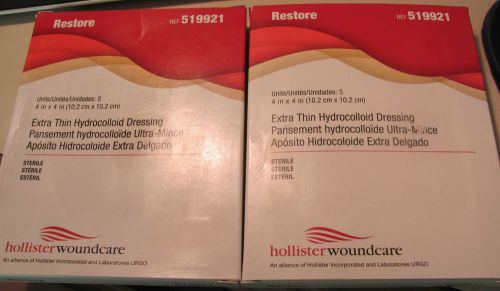

NIB Restore Extra Thin Hydrocolloid Sterile 4x4" Wound Dressing 4 Boxes 20 Pads